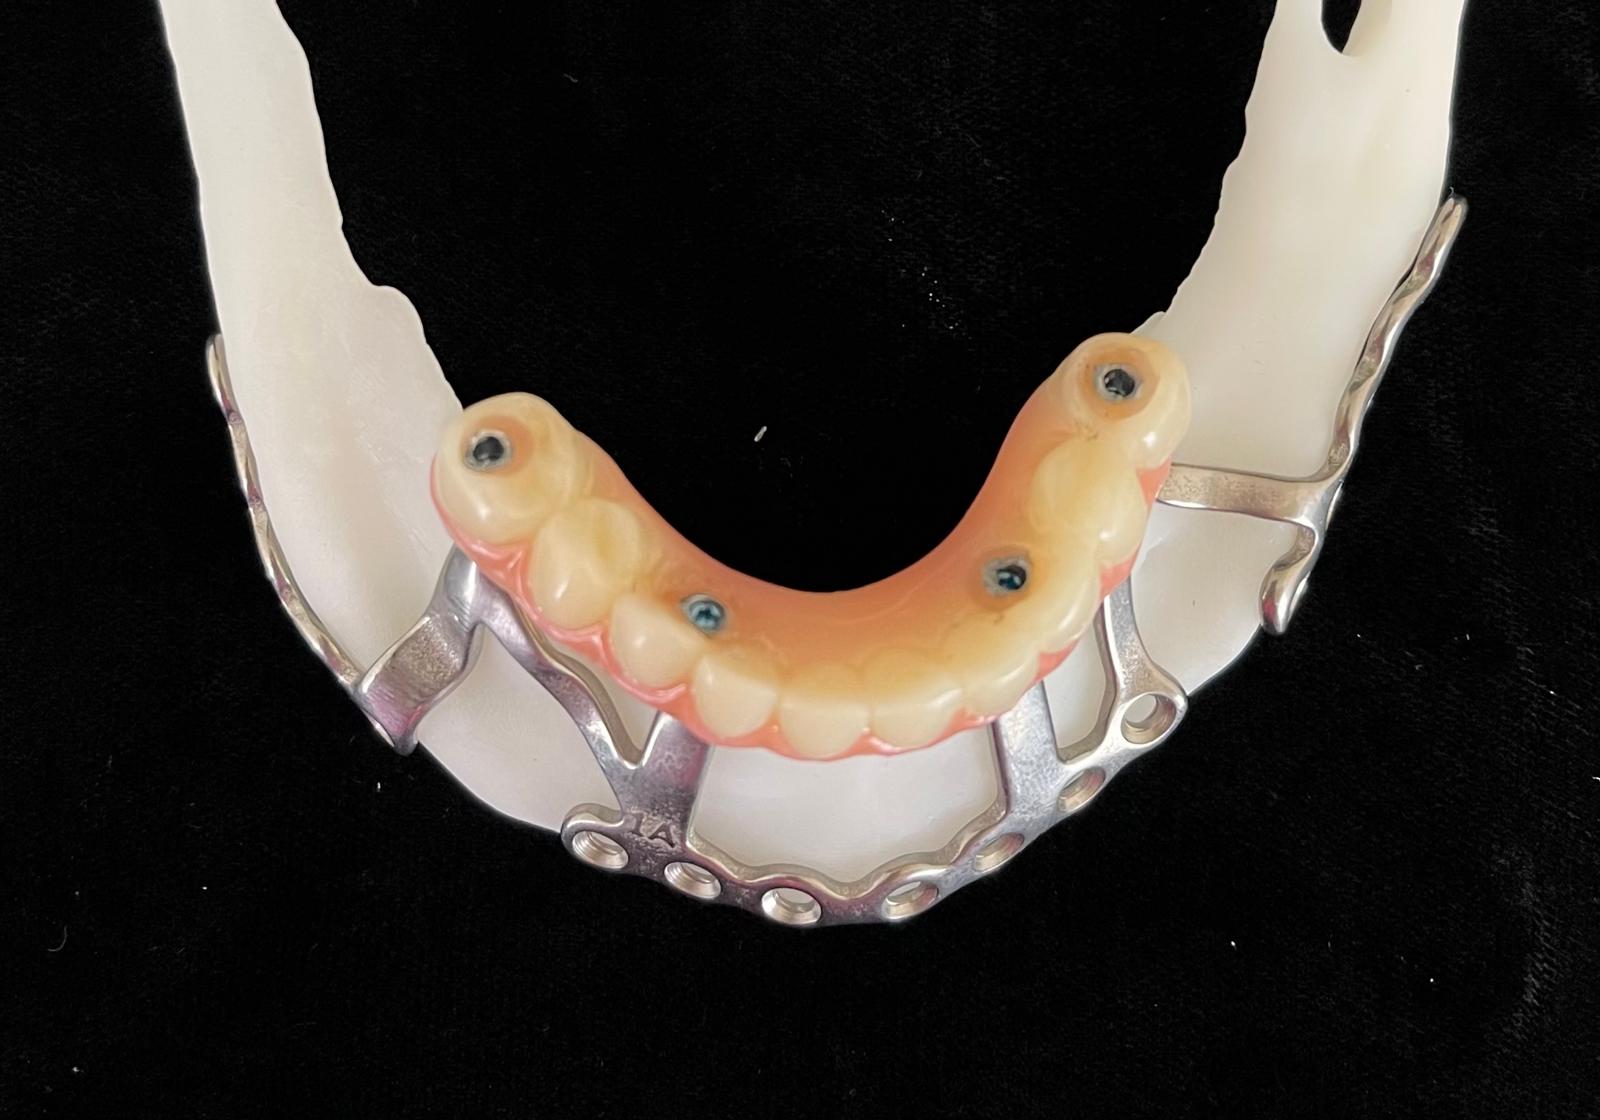

Records for this patient were collected using a dual-scan CBCT and intraoral scanning. A surgical planning session was completed with KLS Martin for the fabrication of a CAD-CAM subperiosteal implant system with immediate loading of a mandibular prototype (Figs 2-5).

A 3D-printed mandibular model with the subperiosteal system and prototype in place was also fabricated (Figs 6 and 7).

A custom occlusal splint confirmed mount and prosthetic space. The site was closed with resorbable sutures intraorally and plain gut at trocar sites. Recovery was uneventful, and the patient progressed to prosthetic rehabilitation (Figs 9 and 10).